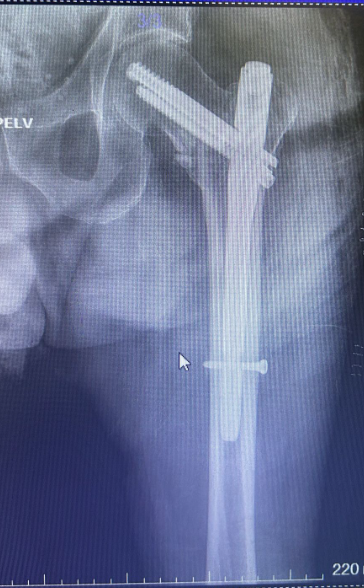

Kalça kırık ameliyatı

Kalça kırık ameliyatı (kapalı)